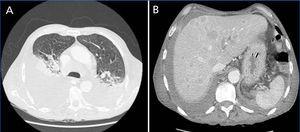

In the post-operative period, the patient developed signs of hyperhydration and started haemodialysis. Hypoalbuminemia and signs of hyperhidration gradually improved, but he maintained severe proteinuria. When clinical euvolemia was achieved, a right pleural effusion persisted. A CT scan was performed, revealing a disseminated neoplasm (Figure 2). A pleural exudate without malignant cells was drained. Tumor markers Ca 19.9 (95.2U/L, normal <27U/L) and neuron specific enolase (NSE) (96.6U/L, normal <15.2U/L) were elevated.

A paraneoplastic syndrome is usually inferred when glomerular proteinuria develops in the six months before or after the diagnosis of malignancy. In our patient, initial evaluation didn’t provide any clue to an underlying diagnosis of malignancy. His systemic manifestations were attributed to severe protein loss, as well as to prolonged periods of hospitalization. Five months after the diagnosis of NS, a right pleural effusion persisted after achievement of euvolemia, and a CT was performed showing a disseminated neoplasm. The patient’s clinical condition had markedly deteriorated and he died of sepsis and respiratory failure within a week.

Figure 2. CT scan